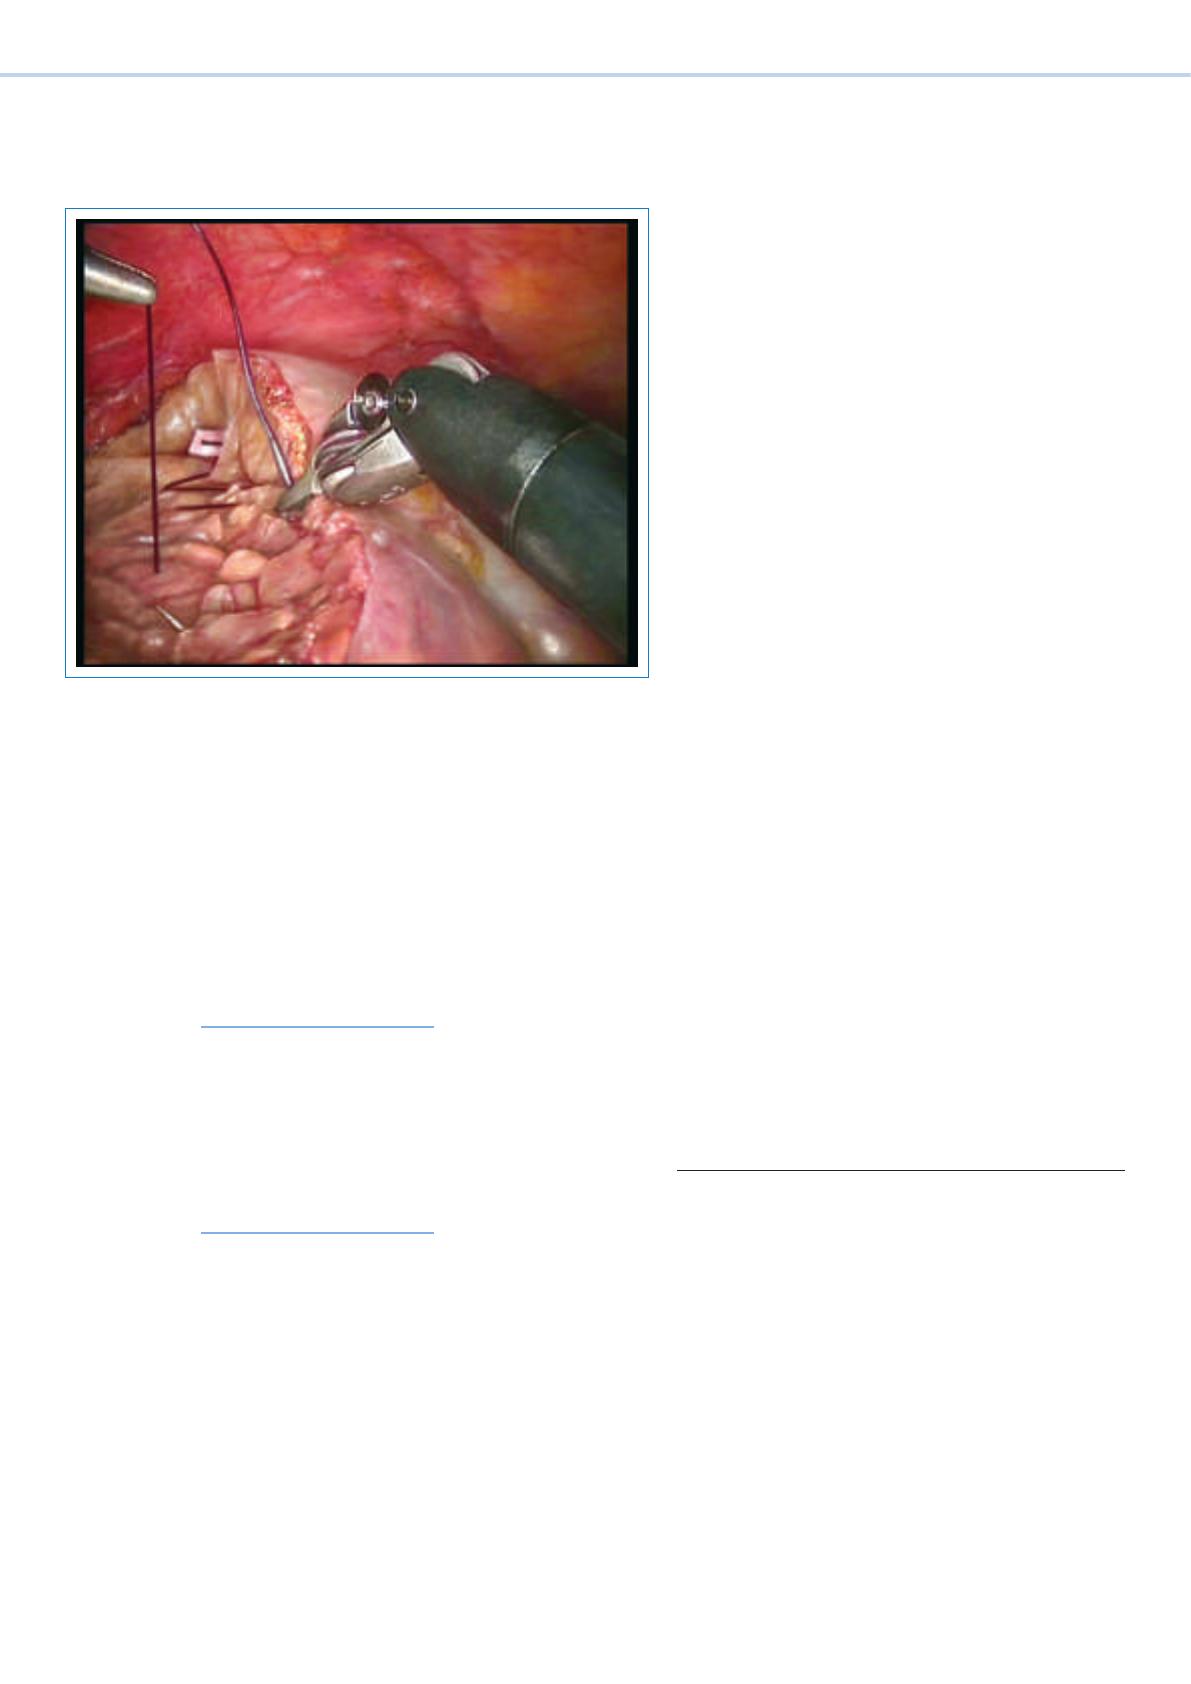

Importance en chirurgie viscérale

Ces dix dernières années, il a été montré qu’en prin-

cipe, toutes les opérations viscérales laparoscopiques

pouvaient aussi être réalisées par chirurgie robotique

[7, 8]. Un nombre croissant d’études indiquent que ces

interventions peuvent être assistées par ordinateurs

pour des résultats cliniques comparables à ceux de la

laparoscopie conventionnelle. L’ un des premiers tra-

vaux à ce sujet concernait la cholécystectomie [17]. Les

véritables avantages du robot chirurgical devraient se

concrétiser surtout en cas d’interventions complexes

qui ont lieu dans un espace relativement étroit [18–20],

notamment en cas de chirurgie colorectale, gastrique,

hépatique et pancréatique, ainsi qu’en chirurgie baria-

trique [19–24]. Ainsi, en cas de résection pancréatique

gauche par exemple, une perte sanguine réduite, un

taux plus élevé de conservation de la rate, ainsi qu’un

taux de conversion inférieur par rapport à la technique

laparoscopique conventionnelle ont pu être montrés [20,

25]. En chirurgie colorectale, l’exécution de sous-étapes

au niveau du petit bassin, ainsi que l’excision mésorec-

tale totale (EMT), semblent, en utilisant la technique as-

sistée par robot, être liées à un taux de conversion infé-

rieur [19]. La chirurgie robotique de la thyroïde présente

également une importance particulière. Entre-temps,

plusieurs groupes ont montré que des strumectomies

assistées par ordinateur étaient possibles par voie trans-

axillaire, sans incision cutanée au niveau du cou [26,

27].